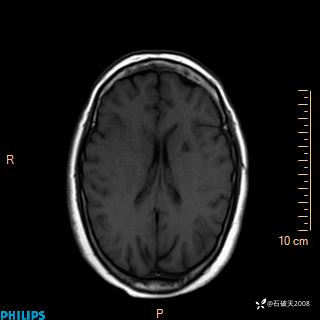

2020.11.14MR

FLAIR